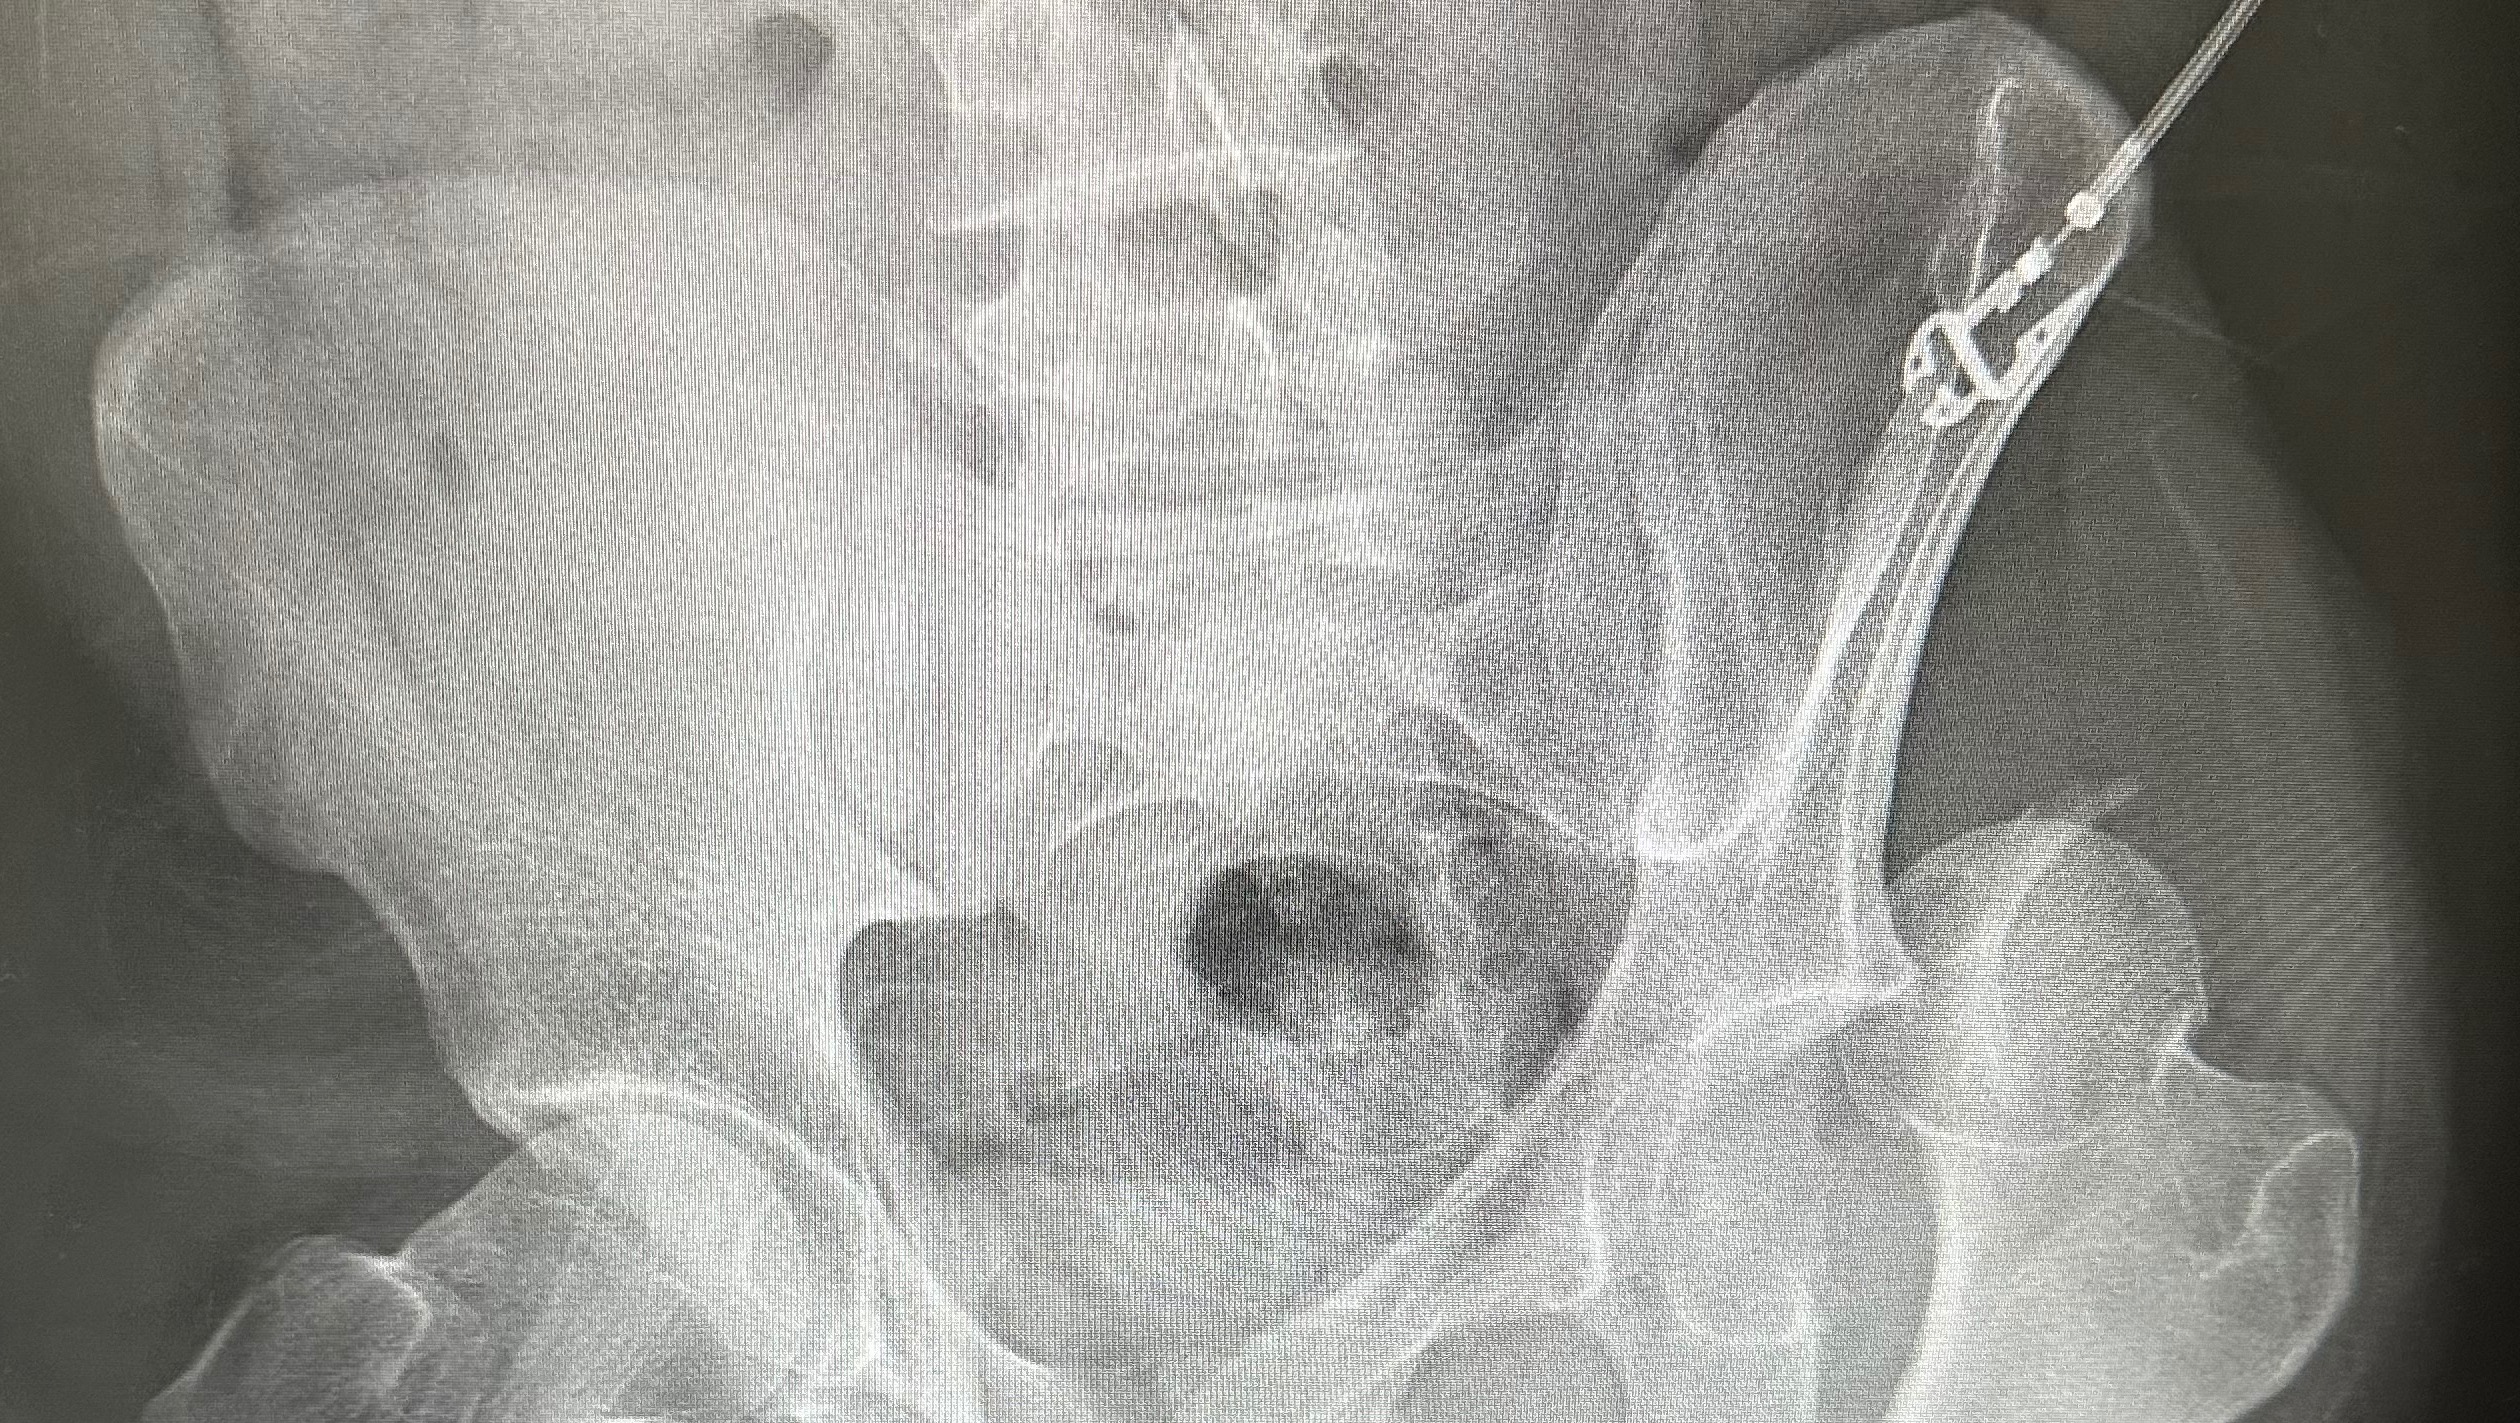

Once at the hospital, it was determined that he broke both of his arms and legs in multiple places, shattered his knee cap, broke his ribs, broke and dislocated his hip, and broke his femur. The only thing not broken is his spirit, pretty face, and desire to face this battle head on. Despite only being able to wiggle his fingers and toes, he still keeps us and the wonderful hospital staff laughing and is a true inspiration.

Brandon has been hospitalized since the accident and following multiple surgeries and some gnarly titanium all throughout his body, he is preparing to go to a rehabilitation center/nursing home to continue healing with months of physical therapy as he is not anywhere near being self-sufficient.